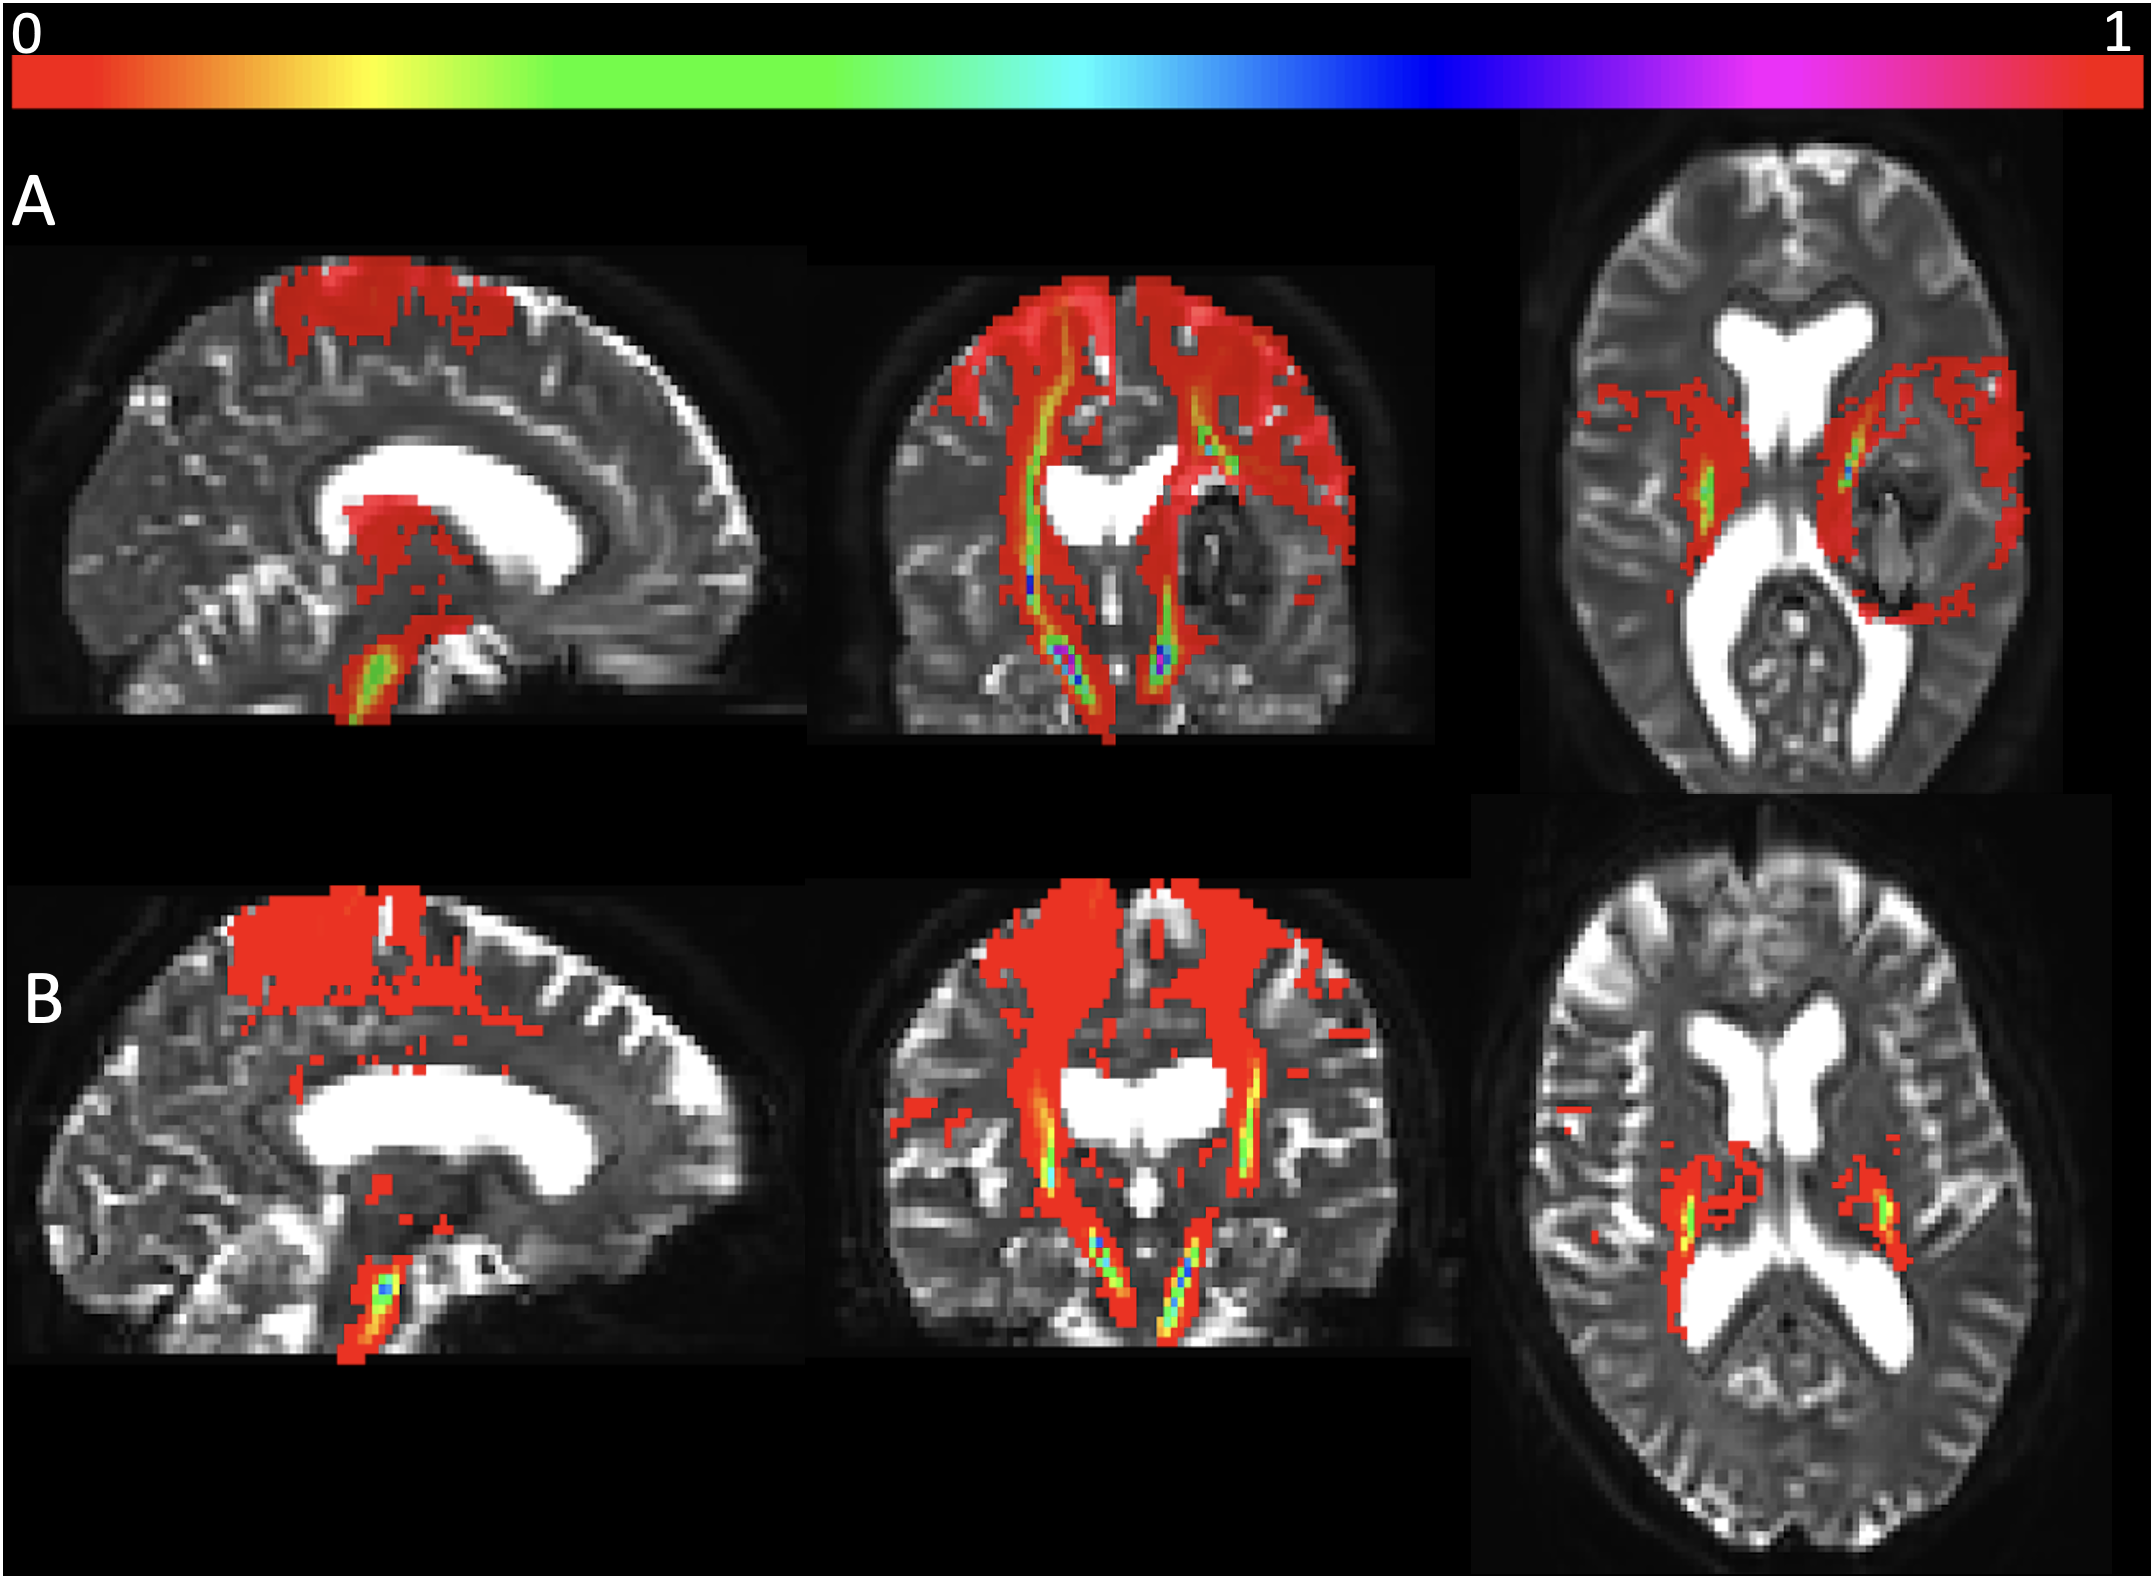

Tractography maps were produced for 80 patients with DTI, T1 and CT imaging. Examples of the CST tractography maps for two patients can be seen in Figure 1. Tractography failed for 10 patients.

Refer to caption

Figure 1: Probabilistic tractography maps of the CST, superimposed onto the b0 volume of the DTI images for A) a patient with a haematoma involving the CST and B) a patient with a haematoma not involving the CST.